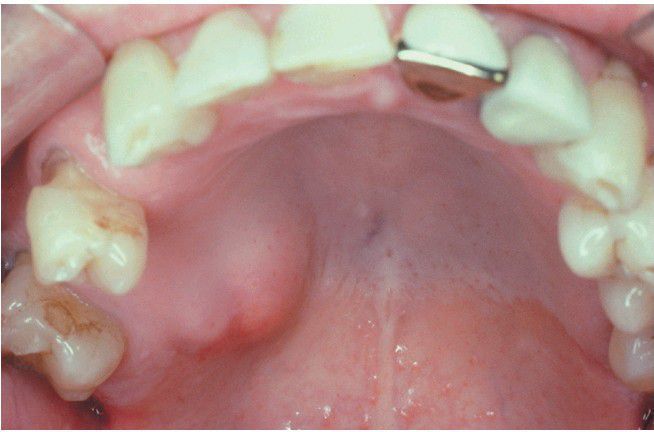

Salivary Adenocarcinoma

. Mass of the posterior lateral hard palate.